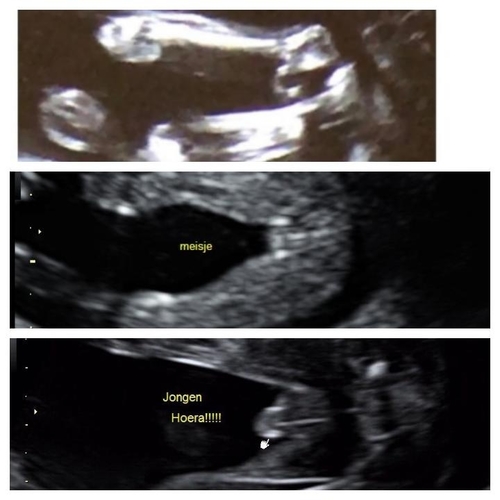

Wauw dit is geen makkelijke. Het geslacht is goed doorbloed op deze foto daarom maakt het het lastig. Ik heb ff wat van internet geplukt ter vergelijking hieronder.

Wellicht dat dit helpt? 😊

Hmm aan de hand van deze foto en haar echo foto denk ik meer een jongen 🙈

De bovenste van de 3 is dus haar eigen echo foto, maar dat had je vast gezien😉

Ik neig ook iets meer naar boy want bij een meisje zou het iets minder 'bol' moeten staan als je Googlet op geslachtsecho meisje .. Het is dan iets 'platter' zeg maar...En in dat bolletje zie je dan nog een streepje zeg maar.

Tenzij deze echo nog echt van onder de 15w is ofzo maar lijkt me niet er staat 20w echo